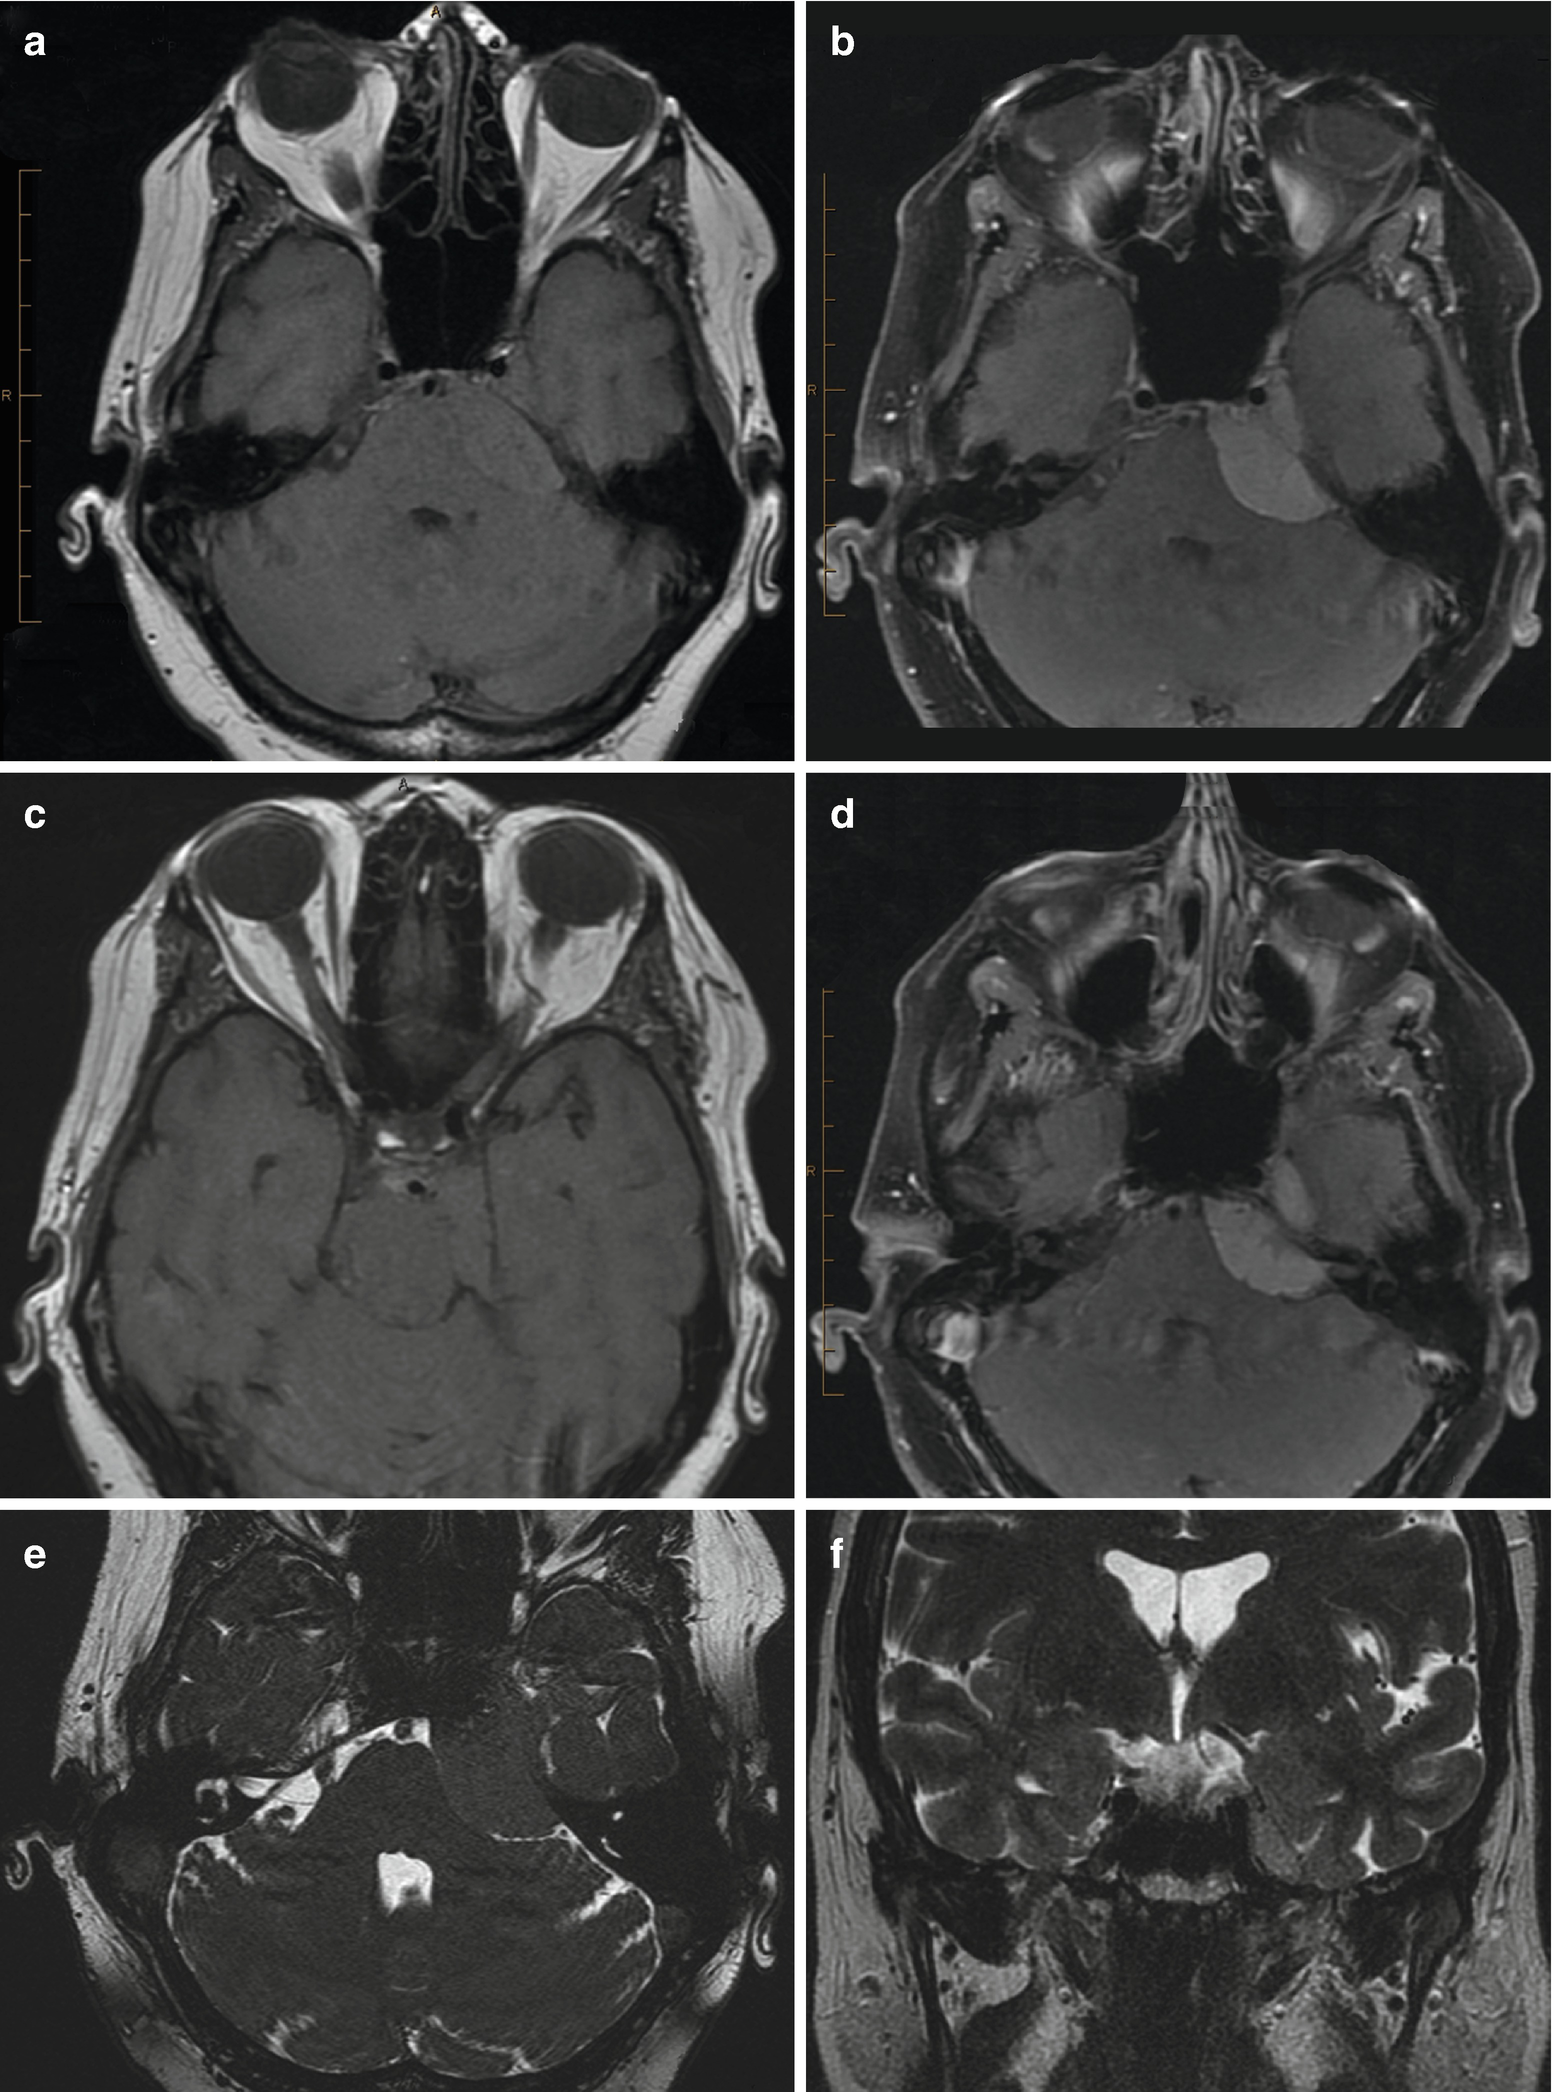

Magnetic Resonance Imaging Of Cerebellopontine Angle Lesions

Imaging Of A Right Cerebellopontine Angle Cpa Calcifying Download Scientific Diagram